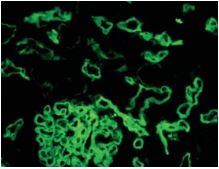

Bio SB has developed a highly sensitive Immunofluorescence and non-biotin monovalent Fab micropolymer IHC detection systems for the detection of IVD antibodies for Complement (C1q, C3c, C3d, C4c, C4d), Serum Proteins (Albumin and Fibrinogen) and Immunoglobulins (IgA, IgD, IgE, IgG, IgM, Kappa and Lambda) related to autoimmune conditions. Our innovative IF and IHC detection systems and high affinity antibodies, have opened the doors for a faster and accurate Immunofluorescence and Immunohistochemistry applicable to Autoimmune Disease like Nephropathies and Lupus.

These antibodies and detection systems are intended for use in Immunohistochemical (IHC) and Immunofluorescence (IF) applications of formalin-fixed paraffin-embedded tissues (FFPE), frozen tissue sections and cell preparations.

InDirect Immunofluorescence Detection

Rabbit FluoroDetector FITC |

Rabbit FluoroDetector FITC with FluoroMounter |

Rabbit FluoroDetector FITC with FluoroMounter with DAPI |